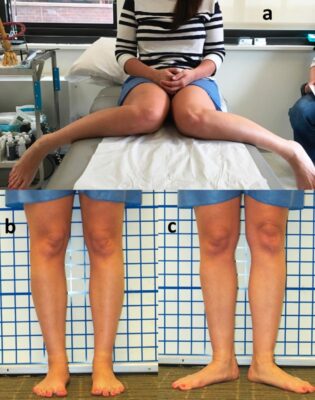

Các vấn đề với cơ chế duỗi bao gồm đau khớp bánh chè đùi, lệch trục, và mất vững. Thuật ngữ lệch trục khốn khổ mô tả một kết hợp giữa vặn trước xương đùi, xoắn vặn xương chày ra ngoài, và tăng góc Q, có thể xảy ra kèm với xương bánh chè di lệch lên trên, xương bánh chè lác trong (squinting patella), gối vẹo trong (chân chữ O), và gối quá ưỡn. Tăng vặn trước xương đùi làm xương bánh chè di lệch vào trong, thay đổi góc nghiêng xương bánh chè (nhìn hướng vào trong, tạo nên lác trong), là làm tăng góc Q, làm tăng lực tiếp xúc bánh chè- đùi. Xoắn vặn xương chày ra ngoài làm lệch lồi củ chày ra ngoài, và cũng làm tăng góc Q. Những bất thường này góp phần gây đau khớp gối.

Quan sát nhanh các biến dạng từ bàn chân (bàn chân bẹt, bàn chân khép …) đến khớp gối (chữ O, chữ X, tư thế bất thường của xương bánh chè) đến khớp háng.

Trong trường hợp vô căn, biểu hiện lâm sàng thường gặp nhất là trẻ đi với ngón chân vào trong (góc tiến bàn chân âm) và xương bánh chè “lác” trong, hay vấp ngã và ngồi với tư thế “chữ W” (hai gối gập và cẳng chân dang ra phía sau. Khám lâm sàng phát hiện góc tiến bàn chân vào trong, tăng xoay trong khớp háng, giảm xoay ngoài, tăng vặn trước xương đùi. Tăng vặn trước xương đùi thường được chẩn đoán sau ba tuổi, cao điểm vào khoảng 4-6 tuổi, và sau đó giảm dần. Tình trạng này thường tự chỉnh khi trẻ lớn lên đến tuổi trưởng thành (>80%), và thái độ xử trí là trấn an gia đình và theo dõi. Thông thường, can thiệp phẫu thuật không được xem xét trước khi trẻ đạt 9–10 tuổi.